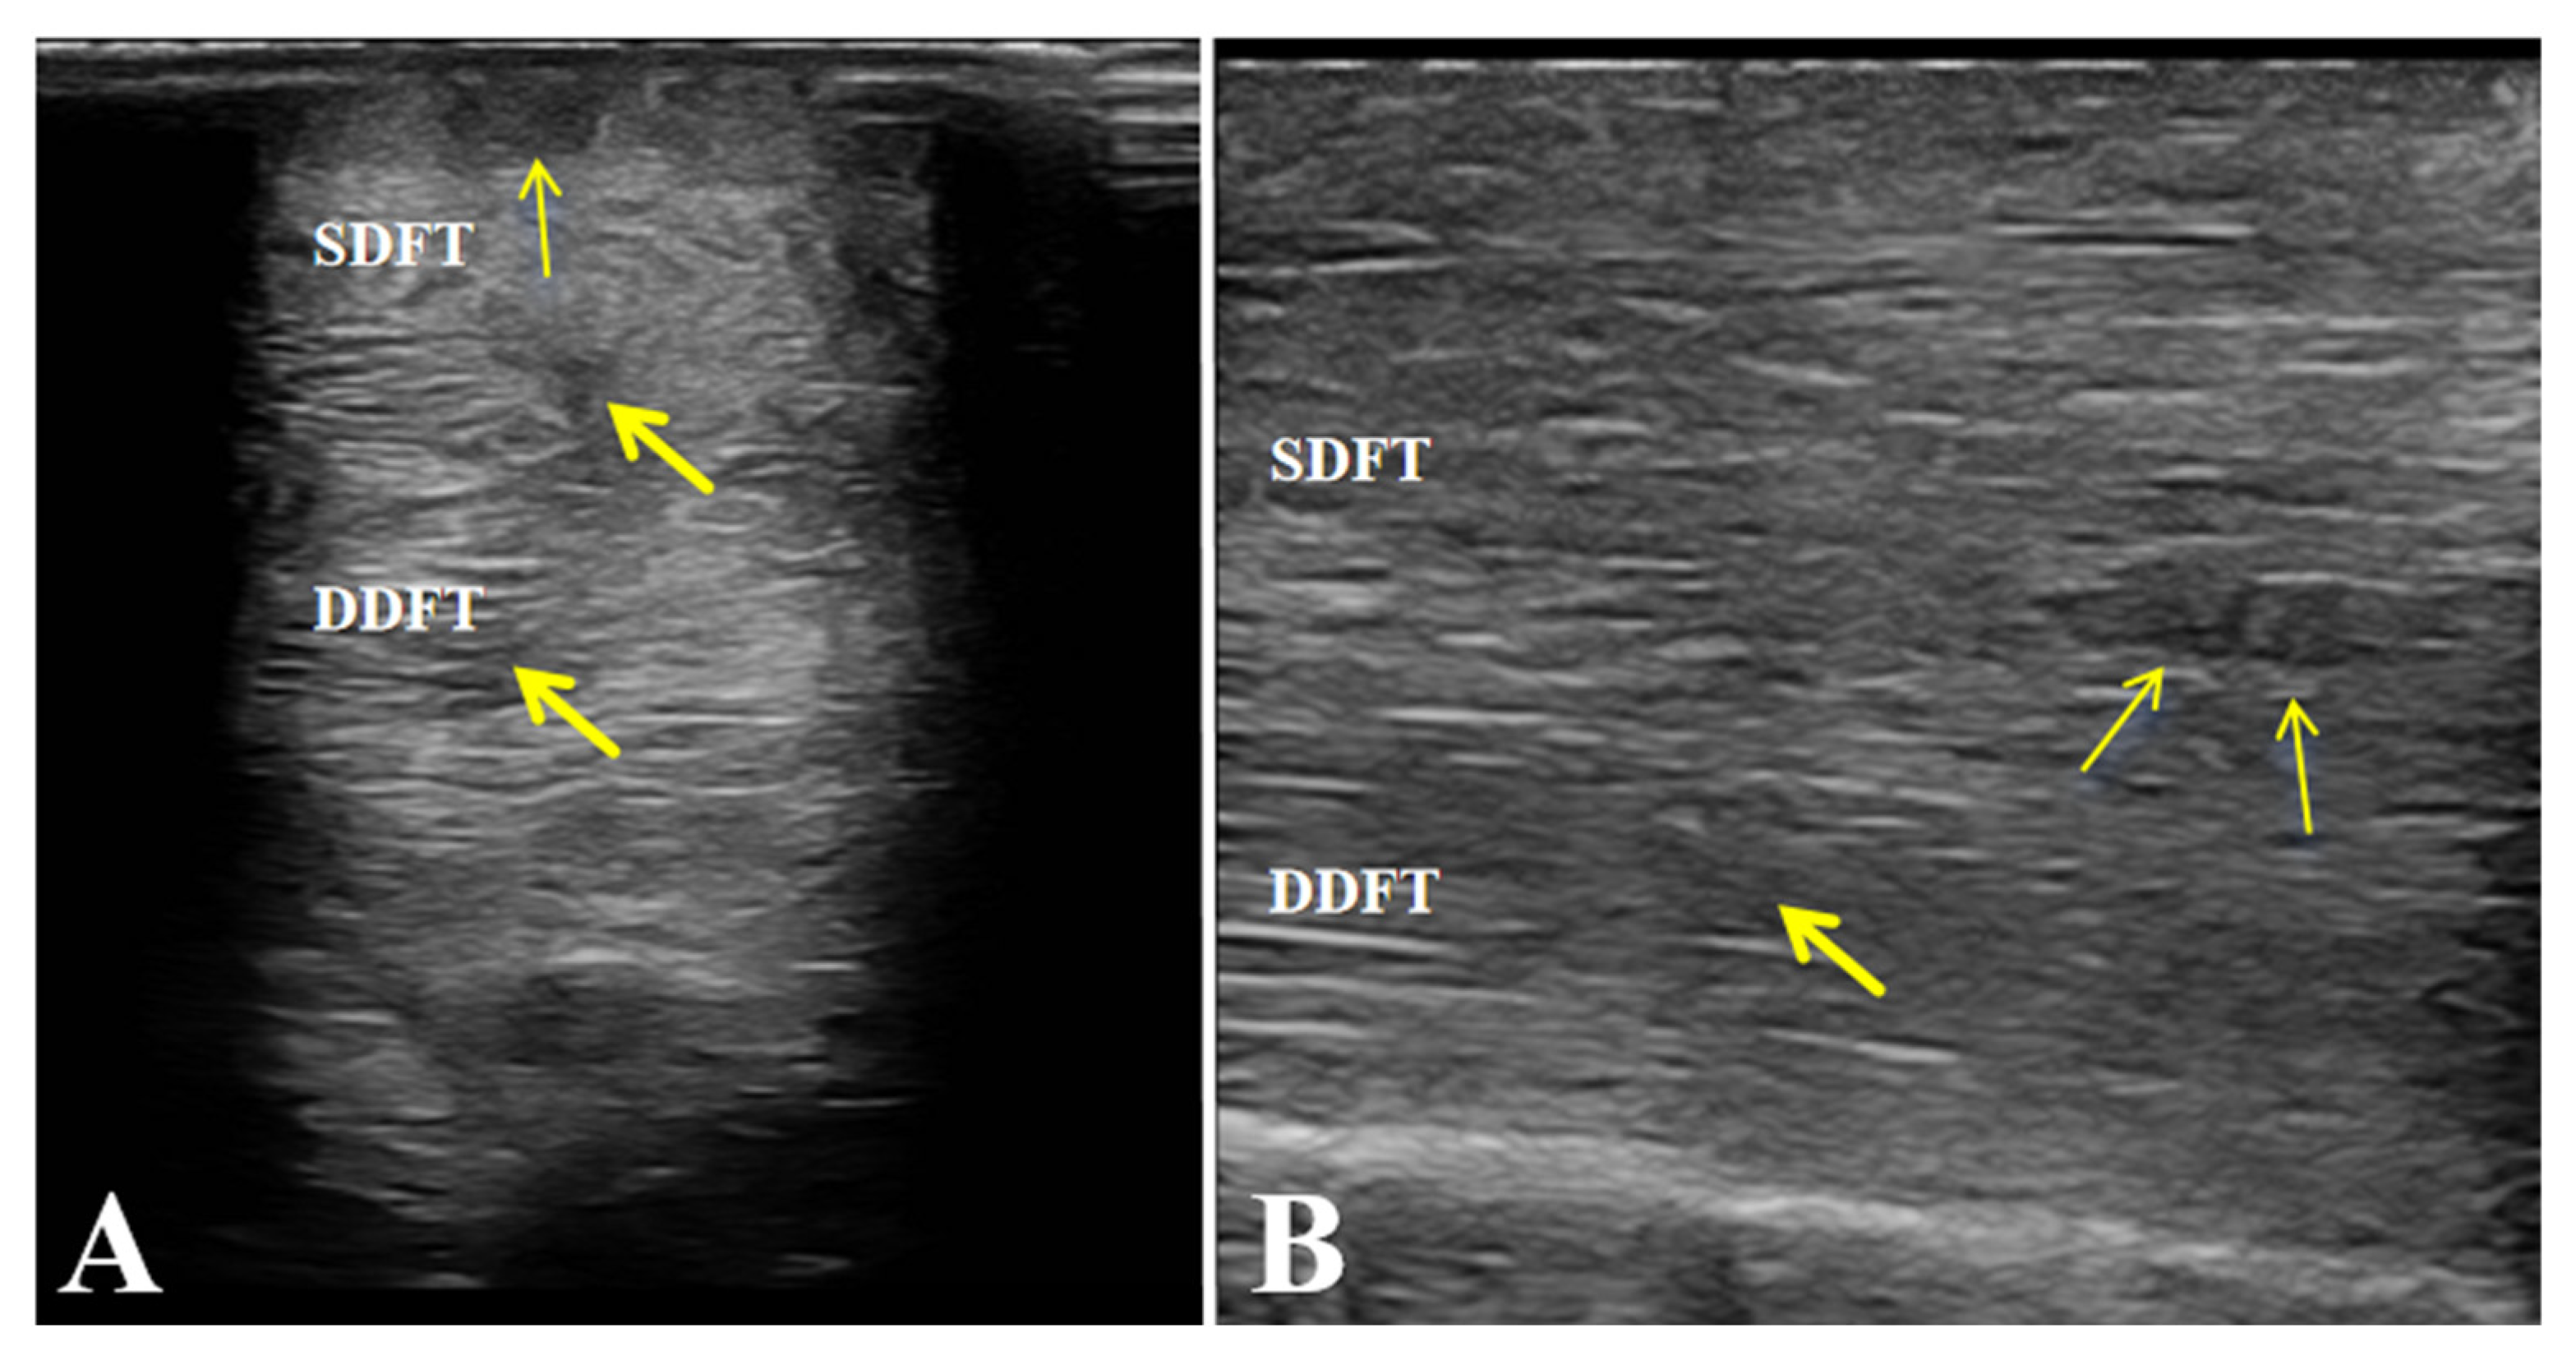

After completing the medication combined with LIPUS-assisted therapy, ultrasonographic examination revealed marked improvement in the overall echogenicity of the affected SDFT and DDFT. Both tendons exhibited uniformly increased echogenicity, with no diffuse hypoechoic areas or regions of heterogeneous echotexture within the tendon substance. The internal homogeneity had become comparable to that of the contralateral healthy tendons. In the sagittal scans, the normal parallel, fibrillar echotexture was largely restored, showing well-organized, continuous fibers aligned with the longitudinal axis of the tendon, without evidence of disruption or fiber-pattern irregularity (Figure 6).

Figure 6. Post-treatment ultrasonographic images of the affected horse. (A,B) Increased echogenicity and uniform fibrillar alignment of the superficial digital flexor tendon (SDFT) and deep digital flexor tendon (DDFT), without fibrosis or adhesions. Arrows indicate the repaired areas of the tendon post-treatment.